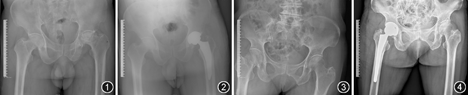

所有THA手术均由一名高年资医生主刀完成,并且所有病例均接受压配型THA治疗(图1,图2)。研究组病例内收肌均挛缩紧张,需要松解;对照组病例内收肌张力正常,无需松解。手术均在全麻下进行,手术入路均为髋关节后外侧入路。术中常规方法安装髋臼侧假体、衬垫和股骨侧假体,保证双下肢达到等长状态(影像学判断、隔手术巾触诊比较双下肢的长度)。然后使用经皮多针刺技术对研究组进行内收肌松解,直至内收肌的张力明显下降,触诊张力正常,髋关节外展达45°,外旋达45°。对照组病例THA术中同样需进行内收肌张力和关节外展外旋活动度的判定,若内收肌张力过大或髋关节活动度未达上述标准,同样需进行松解,但该病例便被排除于本研究之外。

所有病例术后均未出现闭孔神经麻痹现象。术后第2天的超声显示研究组术后内收肌区域无血肿。两组术后2 d、1周均无严重的深静脉血栓出现。3个患者接受了超过60针的松解,术后的内收肌肌力较术前下降,3个月的功能锻炼后肌力回复正常。所有病例均没有深部感染、髋关节脱位、复发性内收肌挛缩等重大合并症出现。直至最终随访时,无假体松动、下沉、穿破皮质和髋关节脱位(图3,图4)。